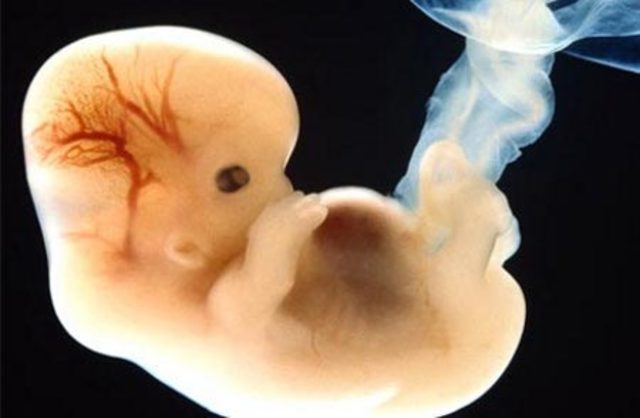

• Día 16 Gastrulación

Día 16 Gastrulación

Formación del proceso del notocordio.

La gastrulación es el proceso de formación de las tres capas embrionarias: ectodermo, mesodermo y endodermo.

A partir de la bástula ocurren una serie de migraciones y fusiones celulares que originan 3 capas celulares bien diferenciadas a partir de las cuales se producirán todos los tejidos del futuro bebé.

• Día 18

Día 18

Nodo de Hensen y fóvea primitiva, notocordio y canal neurentérico, aparición de la placa neural, pliegues neurales e islotes sanguíneos.

Se desarrolla una circulación primitiva entre las vellosidades y el embrión.